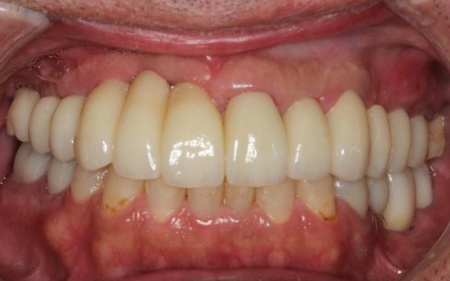

治療後